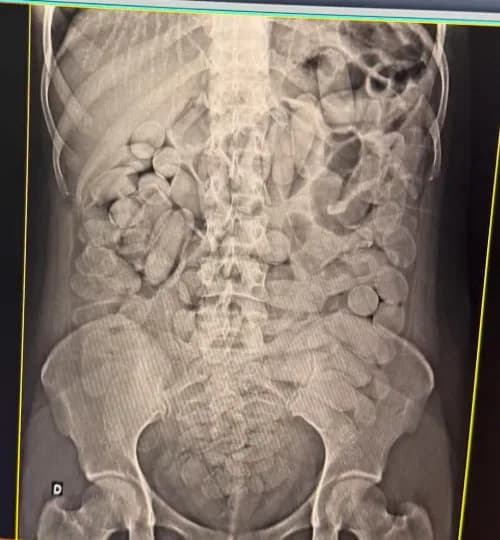

Quatro mulheres foram presas nesta segunda-feira (10/2) ao serem flagradas transportando cocaína dentro do estômago. Elas estavam em um ônibus clandestino abordado durante fiscalização no posto da Receita Federal de Corumbá (MS), na fronteira com a Bolívia.

Ao todo, foram apreendidos 9 kg da droga. Além das cápsulas ingeridas, os agentes encontraram entorpecentes escondidos em palmilhas de tênis, garrafas de energético, cremes de cabelo e até dentro de um sutiã. Outras duas pessoas também foram detidas.

Duas das mulheres foram levadas para o hospital para expelir as cápsulas, enquanto as outras duas foram presas em flagrante. A ação faz parte da Operação Ágata, conduzida pela Receita Federal, Exército Brasileiro e Polícia Militar do Mato Grosso do Sul.